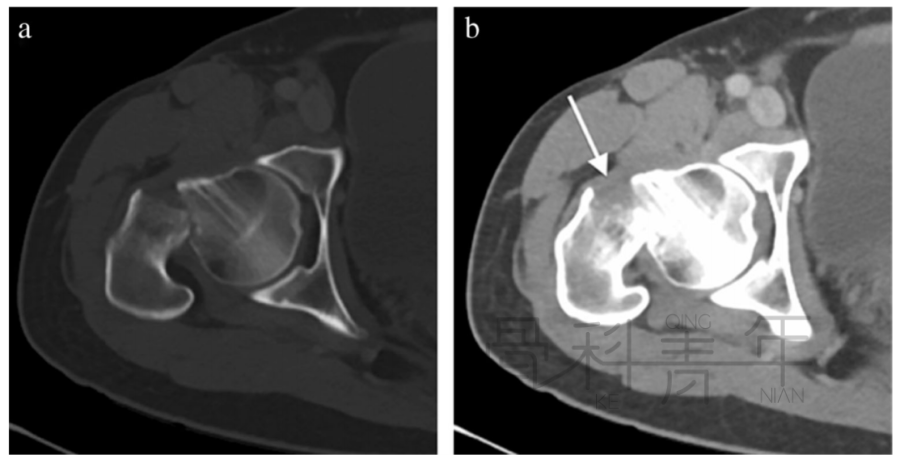

病例4股骨颈骨折,在CT横断面骨窗上未见明显液体分层(a),在软组织窗(b)可见高密度血肿影(箭头所示,CT值为50HU)。